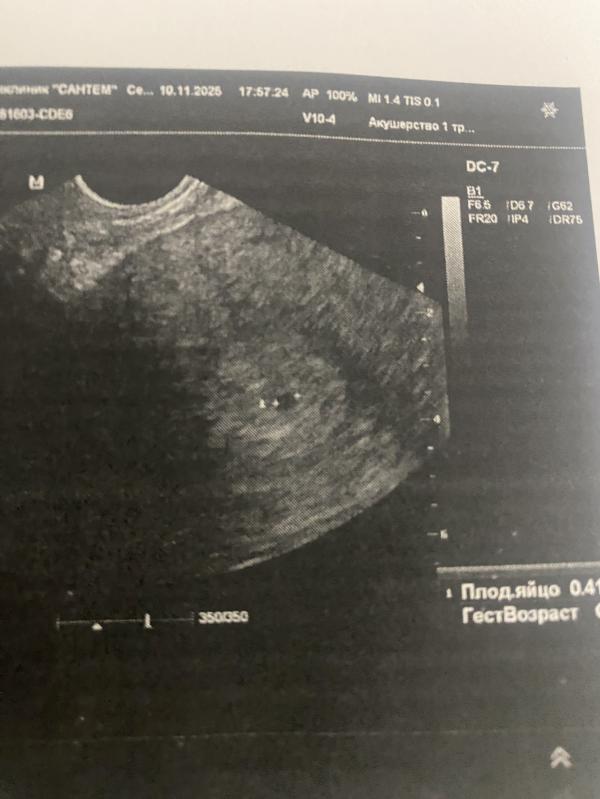

Пришла провериться